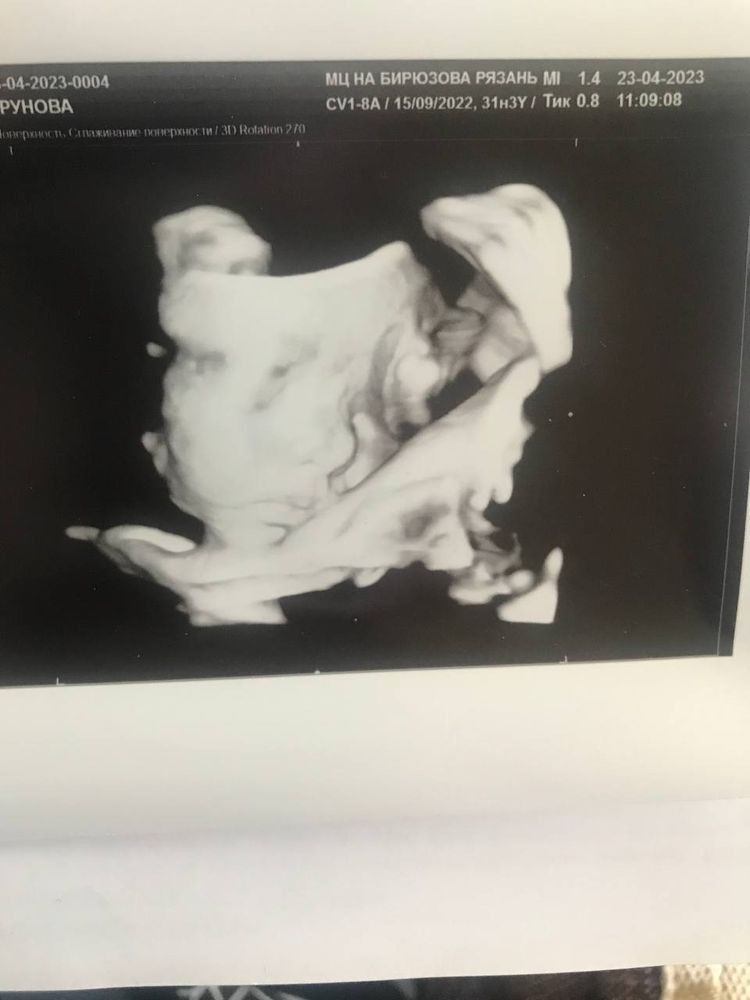

3D УЗИ, когда плацента по передней стенке

Четко все ) на скрининге в 20 недель включали в 3D, уже все отчетливо видно было. И вот вчера смотрели в 24 нед

Изображение Плацента по передней была, узи такое получилось, и ещё видео хорошее)